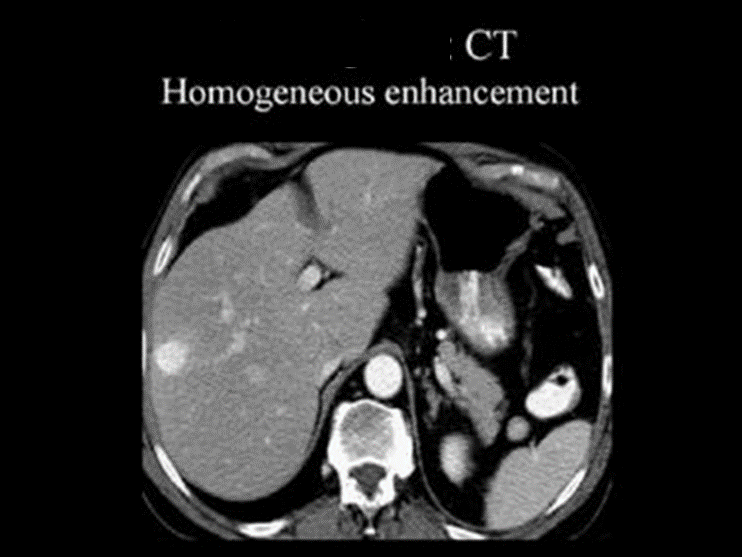

Hepatocellular Carcinoma (HCC)

______ is primary liver cell cancer.

It is most common in those with cirrhosis.

CT is modality of choice for diagnosis.